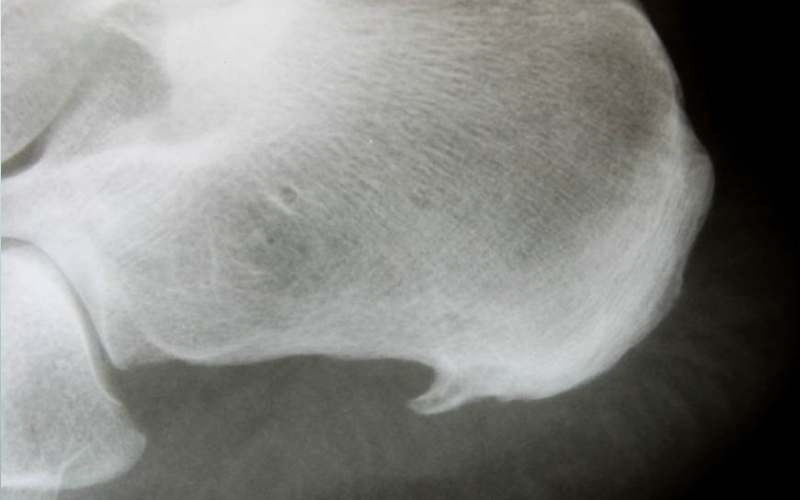

با دیدن علائمی مثل درد و ناراحتی، بدیهی میباشد که باید به پزشک عمومی مراجعه نمایید تا علت را جویا شوید. پزشک عمومی نیز برای اطمینان کامل از عارضه، شما را به پزشکهای متخصص از جمله دکتر ارتوپد و دکتر روماتولوژی ارجاع میدهد. متخصص ارتوپد، تمام عارضههای استخوانی شما را بررسی میکند و متخصص روماتولوژی، به عضلات شما نظر دارد.

با معاینه این دو متخصص، در مرحله پایانی، شما به عکس برداری از عضلات و استخوان خود ارجاع داده میشوید. روشهای عکس برداری میتواند یکی از موارد زیر باشد:

تصویر برداری ام ار آی که از امواج رادیویی برای عکس برداری از اسکلت بدن استفاده میکند

تصویربرداری سی تی اسکن؛ در این تصویر برداری از اشعه ایکس استفاده میشود.